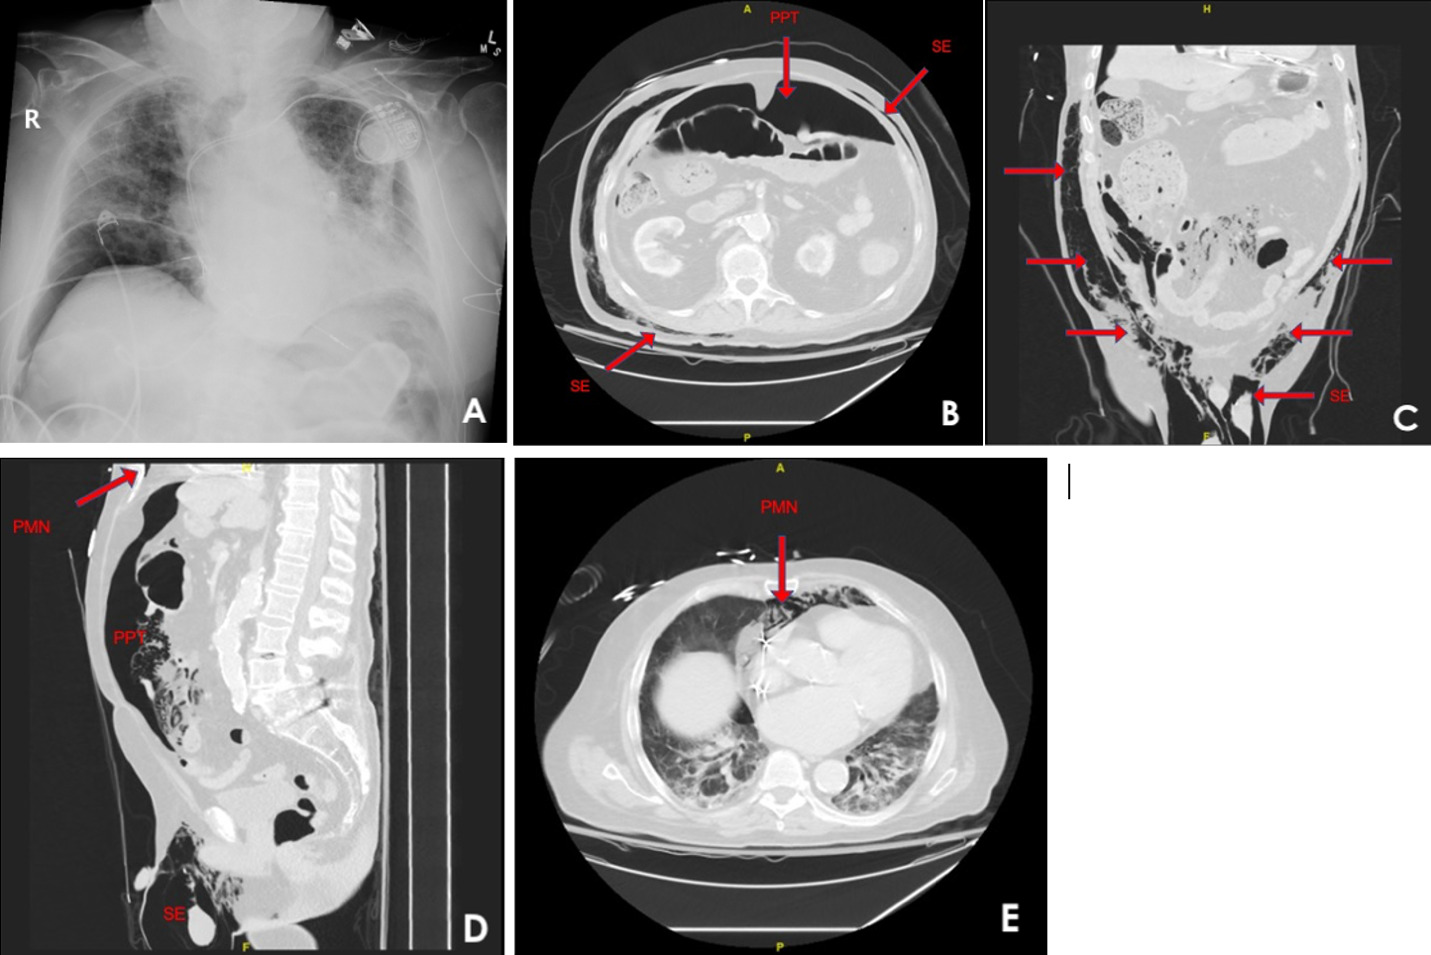

It was noticed that afternoon he had developed abdominal distension and scrotal swelling, for which an immediate screening chest x-ray was performed, showing pneumoperitoneum. This resulted in surgical consultation due to concern for bowel perforation and a stat CT of the abdomen and pelvis with contrast to be obtained [Figure 2]. The CT imaging demonstrated that the appearance of pneumoperitoneum was related to pneumomediastinum and subcutaneous emphysema that extended circumferentially around the abdomen and anteriorly down to the scrotum in the setting of CPAP.

General surgery determined the pneumoperitoneum was not a result of perforation, but rather, due to the use of CPAP. The patient had no peritoneal signs and the pneumatosis and subcutaneous emphysema was determined to be benign. CPAP was considered essential due to worsening of patchy infiltrates on chest x ray thought to be secondary to cardiogenic pulmonary edema due to CHF exacerbation. It was determined the best course of action was to maintain, but limit, CPAP using the same settings two hours a night with HFNC in between. Despite limiting CPAP, the patient’s abdominal x-ray demonstrated worsening of the pneumoperitoneum the following day [Figure 3]. CPAP was discontinued and the patient was maintained on HFNC of 60L on 100% FiO2. He was subsequently discharged to hospice, where the patient subsequently died.

_and_contrasted_ct_scan_of_the_abdomen_demonstrating_(b)_near-circumf.png)